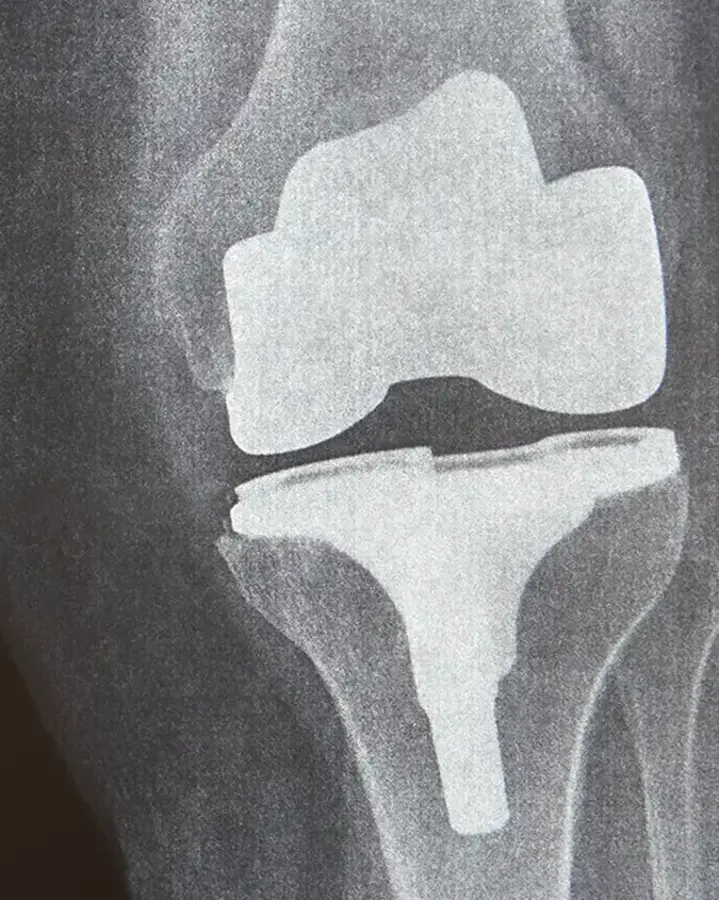

Hip and knee implants can last decades, but sometimes a second surgery, called a revision, is needed. During joint revision surgery, we remove the worn implant, assess the surrounding bone, and rebuild the area with care. Then, we place a new implant to restore your movement and relieve pain.

At United Regional, we specialize in evaluating and treating painful or failing hip and knee implants. Our joint revision surgeons use advanced techniques to remove the old implant, rebuild the affected area, and restore your mobility with a new, secure joint replacement.

X-Ray & Fluoroscopy

United Regional offers advanced diagnostic imaging through X-ray and fluoroscopy — a real-time imaging technique that uses continuous X-rays — ensuring timely and accurate diagnoses.